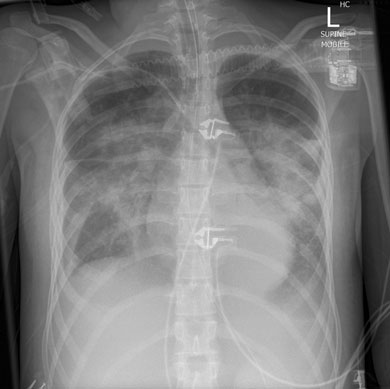

A 17-year-old girl presented to her general practitioner with a 1-week history of fever, arthralgia, general malaise and dry cough. She had a history of systemic onset juvenile idiopathic arthritis (SOJIA), diagnosed at age 2 years and treated with aspirin, and had been in remission for 13 years. She was initially treated by her GP with oral roxithromycin, and admitted to hospital 3 days later with worsening of her symptoms. Her admission chest x-ray (Box 1) revealed bilateral perihilar infiltrates. A diagnosis of severe community-acquired pneumonia was made and broad spectrum antibiotics were commenced, including vancomycin, moxifloxacin, and oseltamivir. Despite this treatment, her condition deteriorated. On Day 3 of admission she required endotracheal intubation and circulatory support with noradrenaline 18–50 μg/kg/min, and was admitted to the intensive care unit (ICU). She remained hypotensive, with a mean arterial pressure of 50 mmHg, and with sinus tachycardia of 132 beats/min, and subsequently required renal replacement therapy. She remained febrile for the first 3 days after admission (temperature range 37.5°C–39°C), and her temperature settled to normal after appropriate therapy was initiated.

This patient presented with fever, prominent respiratory failure and cardiovascular collapse. Her initial systemic symptoms and radiological findings suggested severe sepsis, most likely respiratory in origin, her SOJIA had been in remission for over 10 years, and there was no neurological involvement. These factors made clinical suspicion of MAS difficult, but her hepatosplenomegaly and highly raised ferritin levels suggested the diagnosis, which was supported by her laboratory test results (leucopenia, thrombocytopenia, hypofibrinogenaemia and abnormal liver function test results) and bone marrow aspirate histological findings (Box 2).